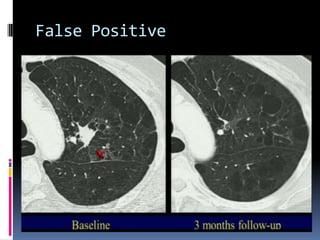

False Positive

 24% of all CT screens = positive

 96% of positive studies = false positives

 36% of all CTs = false positive